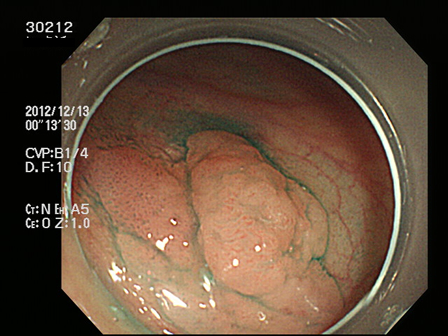

上記100名より抽出した平坦・陥凹型腺腫(=癌化の危険が高いが見落としやすい病変)の内視鏡写真